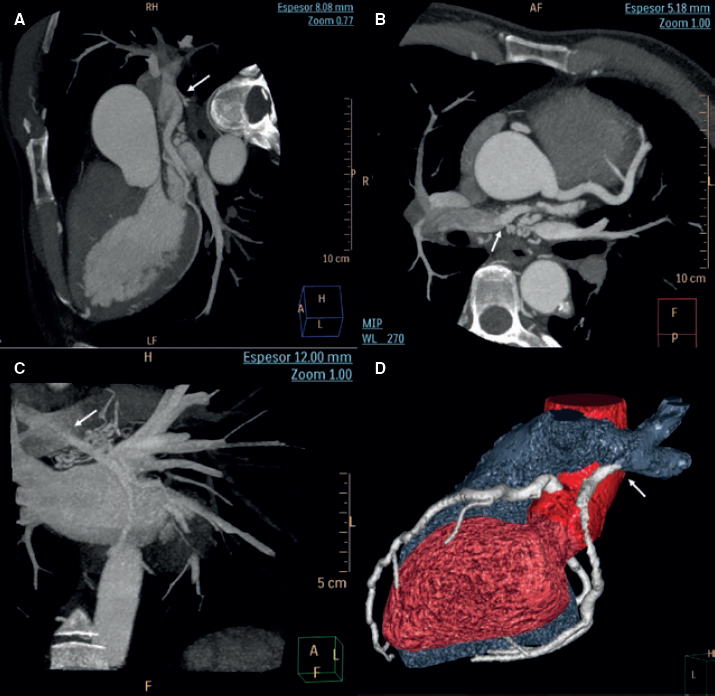

Anomalous origin of left circumflex artery from the right pulmonary …

Cureus | Noninvasive Diagnostic Modalities in an Isolated Case of …

Computed tomography. Huge left circumflex artery to right atrium …

3DCTA in a case of isolated CIA aneurysm. The bilateral superficial …

Functional Assessment of Coronary Artery Disease Using Whole-Heart …

Ultra‑low dose one‑step CT angiography for coronary, carotid and …